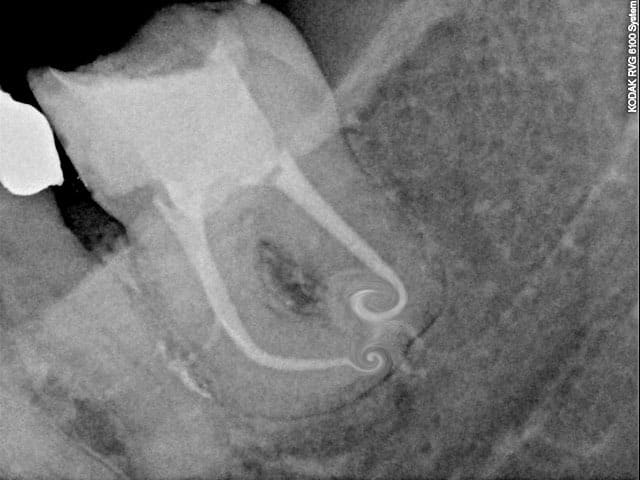

Cas clinique (par un collègue), il utilise sur la presque totalité de ses cas.

--

Céramik

Endo  f2  ghuutc - Eugenol

Un commenaire sur le cas de ton collègue :

1- je ne preconise pas les limes C+ pour explorer le canal ; ce sont des limes de retraitement; trop rigide ; mais c'est une reflexion personnelle.

2- il ne peut pas obtenir cette conicite canalaire avec le seul F2. Soit il traaille egalement avec les Gates de facon appuyée, soit il rajoute un instrument en coronaire (ce qui effectivement a beaucoup de sens). Mais la seule utilsiation du F2 ne permet pas cette mise en forme; notamment dans la partie coronaire.

Le cas est tres beau et repond aux objectifs que je me suis fixé personnellement.